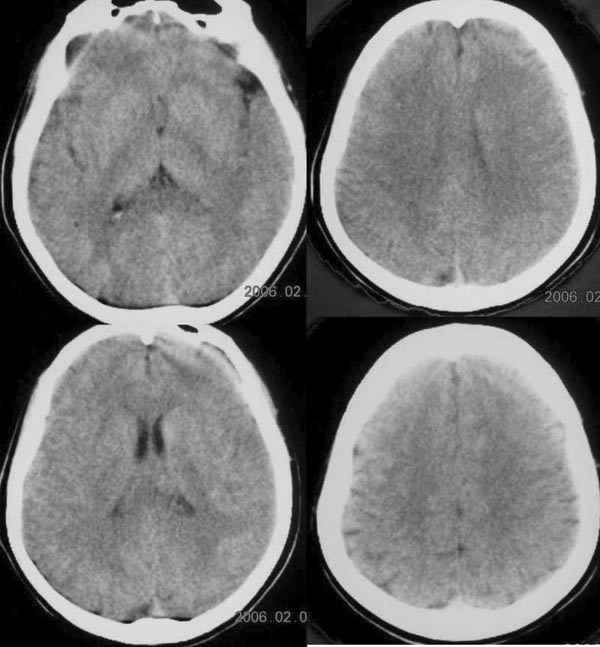

标题: CT2672:[原创]女30岁,头痛右枕部稍高密度影. [打印本页]

标题: CT2672:[原创]女30岁,头痛右枕部稍高密度影.

好像有可疑病灶,做个mr

做mr吧,后颅窝是强项.